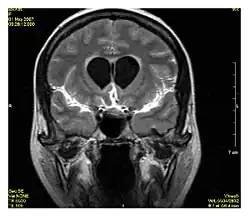

T1 and T2

Each tissue returns to its equilibrium state after excitation by the independent relaxation processes of T1 (spin-lattice; that is, magnetization in the same direction as the static magnetic field) and T2 (spin-spin; transverse to the static magnetic field). To create a T1-weighted image, magnetization is allowed to recover before measuring the MR signal by changing the repetition time (TR). This image weighting is useful for assessing the cerebral cortex, identifying fatty tissue, characterizing focal liver lesions, and in general, obtaining morphological information, as well as for post-contrast imaging. To create a T2-weighted image, magnetization is allowed to decay before measuring the MR signal by changing the echo time (TE). This image weighting is useful for detecting edema and inflammation, revealing white matter lesions, and assessing zonal anatomy in the prostate and uterus.

The standard display of MRI images is to represent fluid characteristics in black and white images, where different tissues turn out as follows:

Signal T1-weighted T2-weighted

High

Inter- mediate Grey matter darker than white matter[35] White matter darker than grey matter[35]

Low